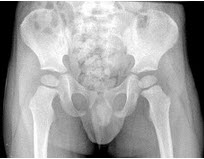

男,根据其正常骨盆影像图像,判断其最可能的年龄()

A.68岁左右

B.58岁左右

C.18岁左右

D.48岁左右

E.28岁左右